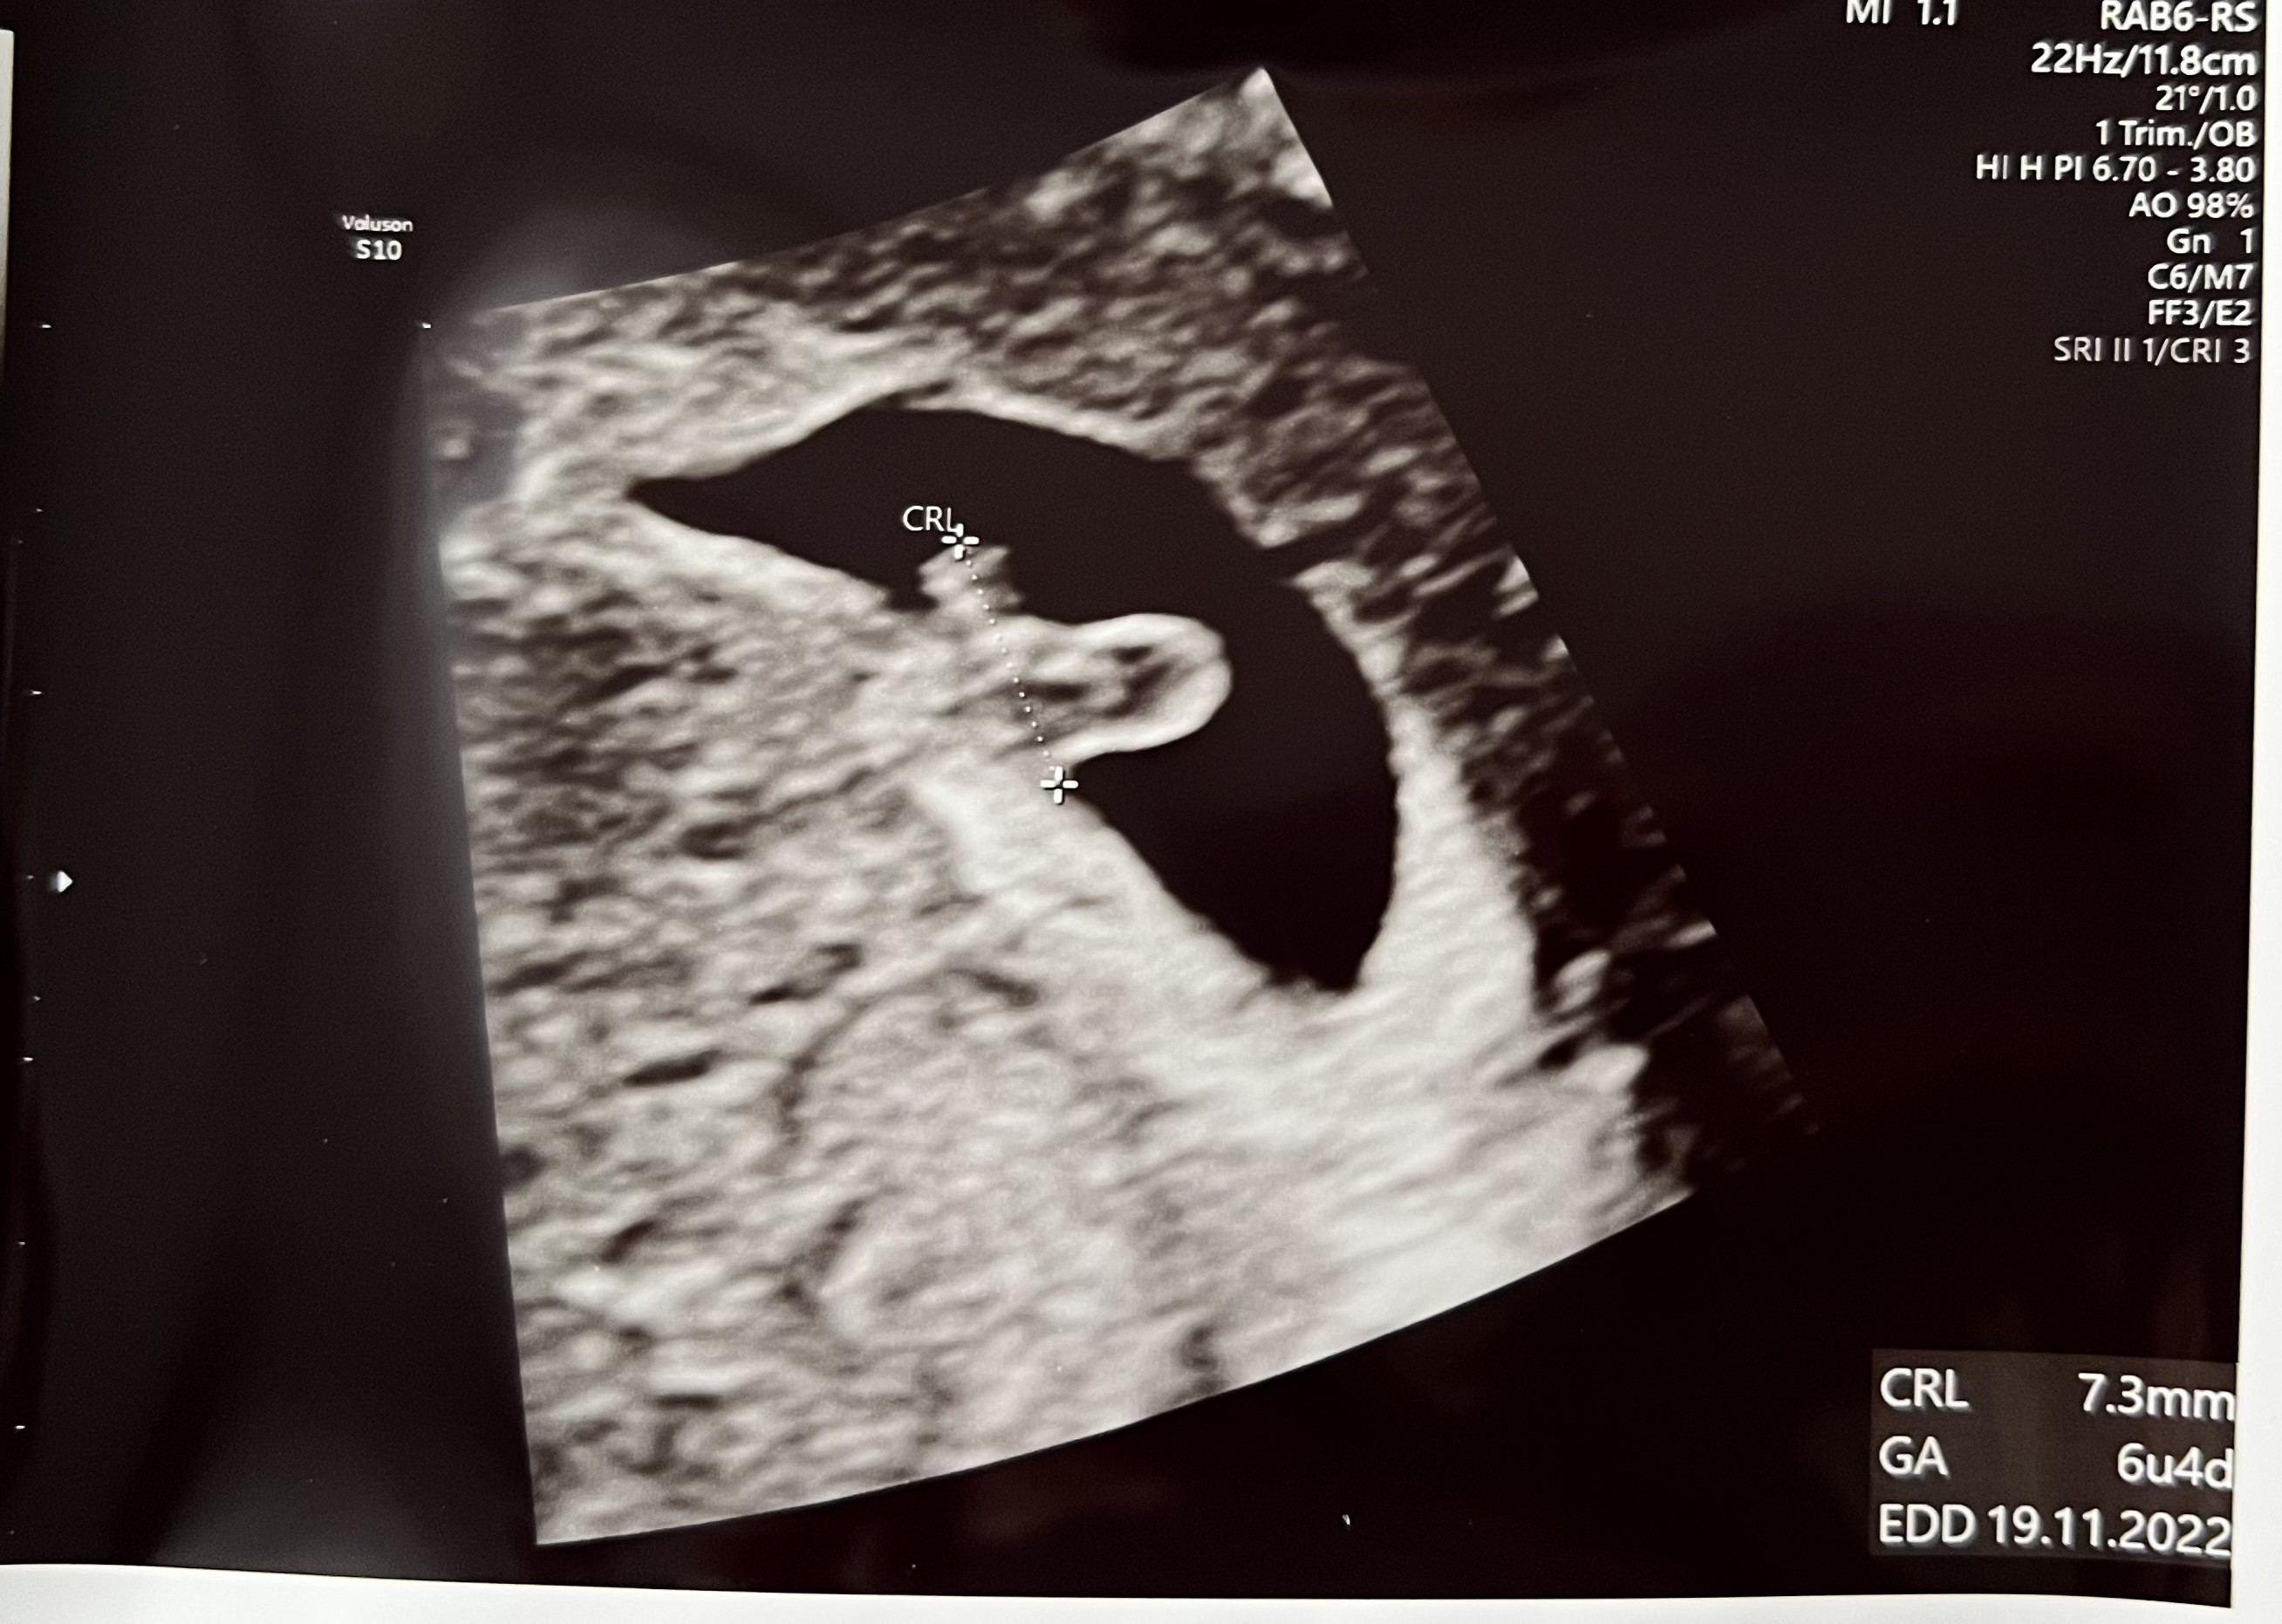

Ja wczoraj miałam wizytę. Pięknie bije serduszko

Wg USG ciąża ma 6 tygodni 3 dni. Jest tydzień młodsza niż z OM. Lekarz mówi że wszystko jest w porządku, po prostu coś się w cyklu poprzesuwało.